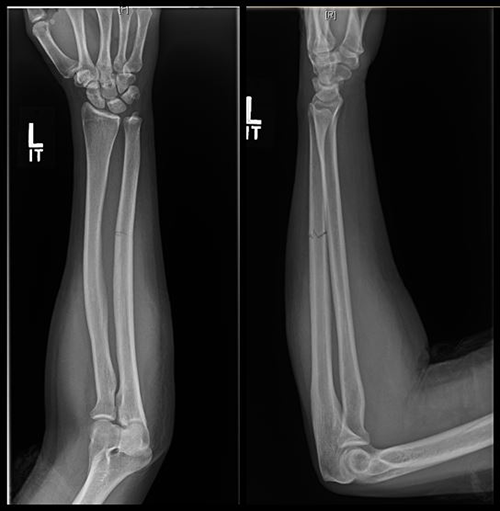

Review of reports by two experienced emergency radiologists revealed that both intimate partner violence and suicidal behavior played independent roles in doubling the overall injury rate compared to that of patients without a history of intimate partner violence or suicidal behavior. Patients with intimate partner violence often sustained head, face, neck and upper limb injuries—areas commonly hurt during assaults.

Intimate partner violence patients with suicidal behavior suffered over six times as many head/face/neck injuries, almost four times as many spinal fractures, three times as many deep injuries, and twice as many upper extremity injuries. These patients experienced almost twice as many severe injuries and three times as many mild injuries.

When looking at independent effects of intimate partner violence versus suicidal behavior, the researchers found that suicidal behavior had a greater impact on the injury rate of upper extremity injuries, while intimate partner violence had a greater impact on head/face/neck injuries.